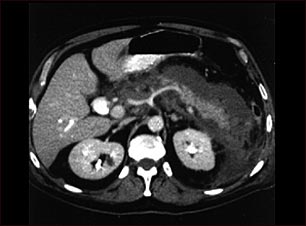

Pancreatitis aguda; TC

Esta TC del abdomen superior muestra un páncreas inflamado e hinchado debido a infección aguda (pancreatitis).